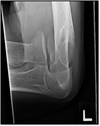

84

Radial head fracture